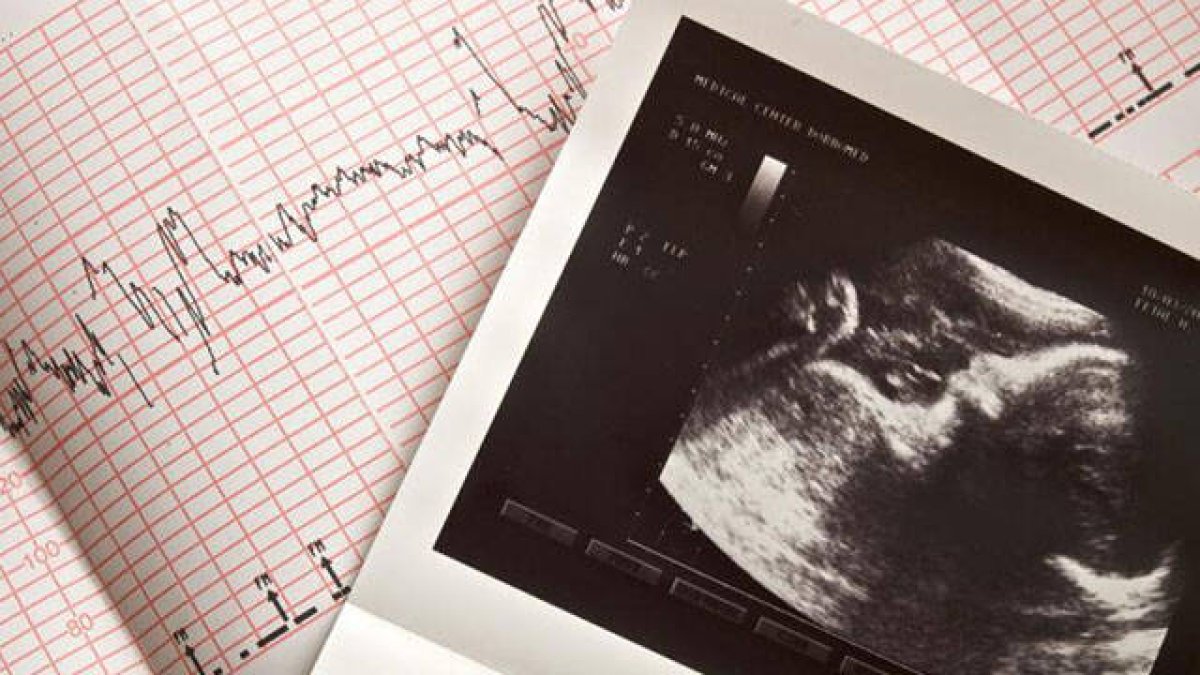

Cardiograma con información de los latidos del corazón de un bebé

El proyecto de ley requiere que cualquier persona que realice un aborto primero realice una ecografía para evaluar los latidos del corazón fetal. Si se encuentra uno, abortar al bebé de todos modos sería un delito grave por el cual un abortista podría perder su licencia médica. El proyecto de ley contiene excepciones por violación, incesto, amenaza médica a la madre o anomalías fetales consideradas “incompatibles con la vida”.